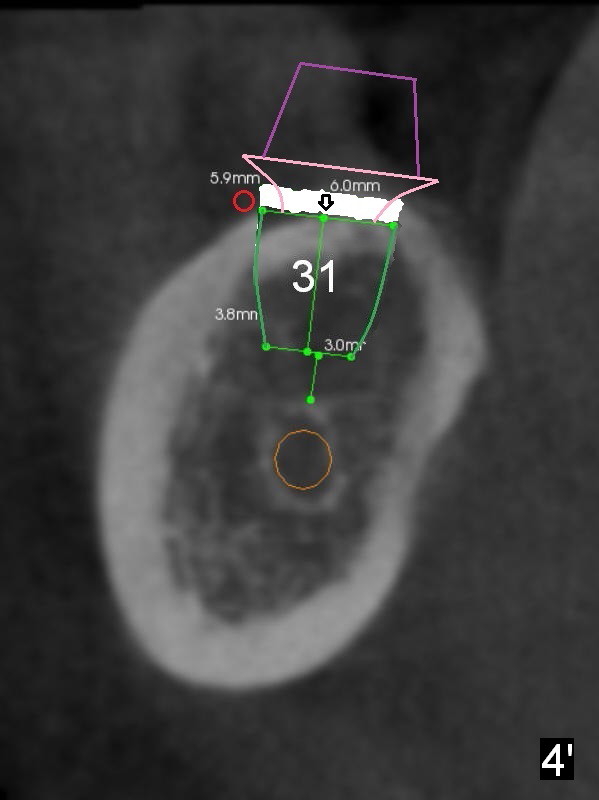

Fig.2 (sagitttal section) shows that the bone height at the site of #31 is shorter than that of #30. There is a 1 mm separation from the Inferior Alveolar Nerve (brown) if a 8 mm implant is placed at #31 (Fig.2,3 (coronal section)), whereas 3 mm separation for a 6 mm implant (Fig.4). Since the tooth #2 is supraerupted, the shorter implant at #31 is more appropriate. It is placed a little deeper (Fig.4' arrow) so that the abutment or the opposing tooth does not need to be trimmed too much. In addition, choose a widest abutment (purple, e.g., 7.8 mm) with the shortest cuff (pink, 1 mm). A splinted immediate provisional will be fabricated to prevent the gingiva from growing into the abutment margin. At restorative phase, a smaller abutment will be used (e.g., 5.8 mm) so that the gingiva is clear from the margin. It will be easy for impression. Then the provisional will be relined to keep the gingiva from growing into the space just created by changing abutments. Bone graft will be needed buccal to the implant at #31 (Fig.3,4 red circle; L: lingual).